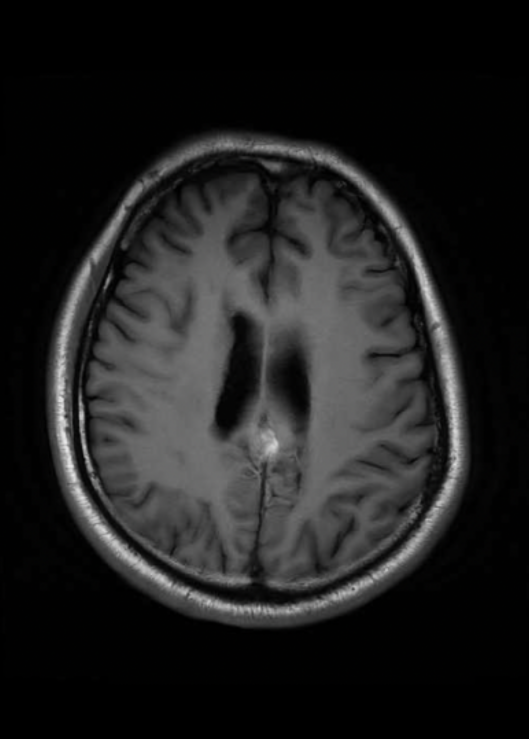

在康复医学科执行主任樊永梅指导下,科室主治医师李慧立即为患者进一步进行腹部脏器和脑部检查。最终,发现患者头颅磁共振可见虫体移动的隧道征,腹部CT发现肝脏两个团块状病灶,考虑寄生虫感染病灶可能。得到这些线索后,康复医学科邀请桂林市疾控中心及医院神经外科、神经内科、放射科、消化内科、病理科、院感中心驻桂湘雅专家进行多学科大会诊。经过综合分析,专家团队诊断考虑患者为脑寄生虫病。同时脑部病变病理检查结果显示,患者大量急慢性炎症细胞浸润,局灶有微脓肿形成,以淋巴细胞、中性粒细胞为主,散布嗜酸性粒细胞,考虑寄生虫病变可能。